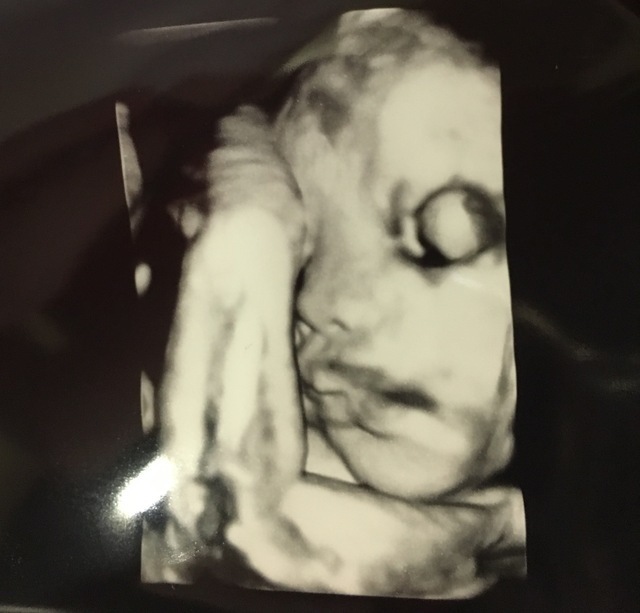

34週3日(34w3d・男の子)|hinaminaママ さん(23歳)

エコー写真撮影時のエピソード:

里帰り先の病院にて、初めての4dエコー。顔が見られるかとドキドキしながら診察を待っていました。

診察台に乗っていざ…先生が突然笑い出し何事かと思えば… 「ある意味すごくわかりやすいよー!今から喧嘩売ってるとか大物になりそう。」と笑いながらモニターを私の方に向けてくれました。

こんなはっきり映るものかと文明の力に感動した反面、確かに拳で喧嘩売ってるようにも見え、将来心配になりました。主人は息子のことよりも文明の力のことばかり話していました。

そんな子がいまではお兄ちゃん!喧嘩もするけど、今のところ拳を突き上げるような感じではなく優しく育っています。